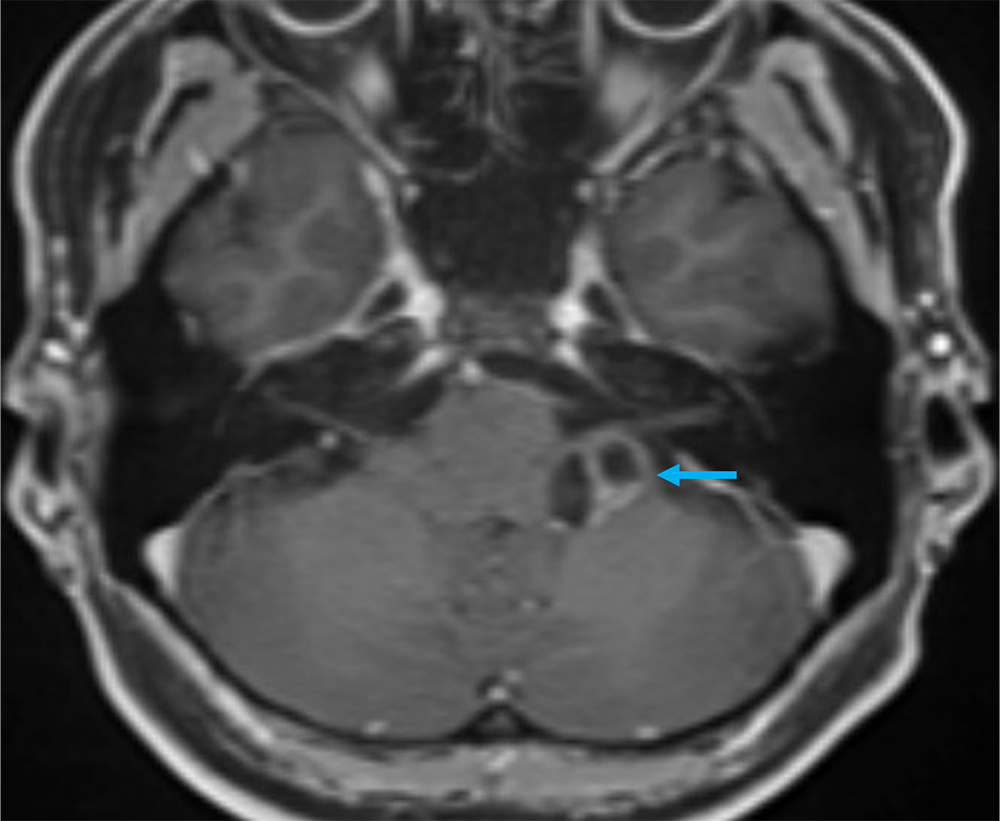

40歳代、女性、55kg、pilocytic astrocytoma

2か月前から頭重感および嘔気が持続しており、他院の単純CTにて左小脳腫瘍が疑われた。当院紹介となり、造影MRIが撮影された。

本症例では左小脳延髄角部に嚢胞成分を伴う腫瘍が存在し、左下位脳神経からの発生、もしくは小脳実質内腫瘍の鑑別が重要であった。前者であれば神経鞘腫、後者であればpilocytic astrocytomaの可能性が高くなる。3Dの脂肪抑制T1強調画像を撮影し、小脳実質内の可能性が高く、pilocytic astrocytomaを上位に考えた。手術が施行され、無事に完全摘出され上記の診断となった。

当該疾患の診断における造影MRIの役割

小脳腫瘍の鑑別において、造影MRIは必須である。本症例のように若年者の小脳実質内腫瘍の場合、特に血管芽腫との区別が重要となる。血管芽腫も嚢胞成分を伴う腫瘤を呈することが多いが、充実成分は強い造影効果を呈する。本症例は血管芽腫を疑うような強い造影効果とは言えず、pilocytic astrocytomaを疑うことが可能であった。